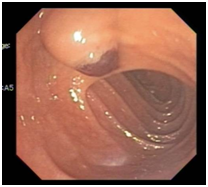

An 11-year-old girl with history of sickle cell trait and allergic rhinitis presented to the emergency department for pruritus. She had been evaluated at an urgent care clinic three weeks prior for generalized rash and pruritus, and was diagnosed with contact dermatitis. At current presentation, rash had resolved but she had persistent pruritus. No abdominal pain. She had scleral icterus, but family reported this was not uncommon as it occurred for over a year and seemed to get worse with her “seasonal allergies”. Initial assessment showed a thin nontoxic appearing girl with normal vital signs and an exam significant for icteric sclerae, excoriations but no rash, and a nontender abdomen with liver palpable 2cm below the right costal margin. Laboratory results showed elevations in direct bilirubin, alkaline phosphatase, and GGT. Ultrasound showed intrahepatic biliary dilation with an echogenic area in the common hepatic duct suggestive of sludge. She had a magnetic resonance cholangiopancreatography (MRCP) that showed diffuse dilation of the intrahepatic, common hepatic, and common bile ducts; a distended gallbladder; and a T2 hypodense lesion in common bile duct extending into common hepatic duct that was consistent with biliary sludge (Figure 1), with suspicion for choledochal cyst. She then had an upper endoscopy, which was significant for a lesion protruding from the ampulla that had the appearance of a blood clot. It was extracted after sphincterotomy, and noted to have a thin stalk-like attachment, measuring 1.3cm in length, which was partially resected and sent to pathology (Figure 2&3). Pathology was significant for a polypoid tumor with variable cellularity, and “tadpole” shaped cells having cytoplasmic cross striations, and a high proliferative index by Ki67 stain. These findings were diagnostic of a botryoid variant of embryonal rhabdomyosarcoma. She was started on chemotherapy with vincristine, adriamycin, and cyclophosphamide (VAC), and improved with this regimen. She has not required surgery or radiation (Figure 4A-4C).

Figure 3 Endoscopic retrograde cholangiopancreatography (ERCP).